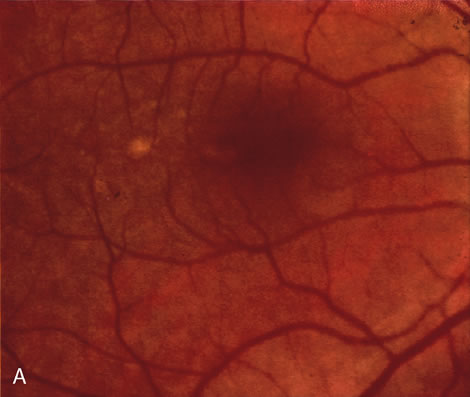

zone in senile macular degeneration. Am J Ophthalmol 93:157, 1982. 8. Yannuzzi LA, Negrão S, Iida T et al: Retinal angiomatous proliferation in age-related macular degeneration. Retina 21:416–434, 2001. 9. Fernandez LH, Freund KB, Yannuzzi LA et al: The nature of focal areas of hyperfluorescence or hot spots imaged with

indocyanine green angiography. Retina 22:557–568, 2002. 10. Ghazi NG. Retinal angiomatous proliferation in age-related macular degeneration. Retina 22:509–511, 2002. 11. Axer-Siegel R, Bourla D, Priel E et al: Angiographic and flow patterns of retinal choroidal anastomoses in age-related

macular degeneration with occult choroidal neovascularization. Ophthalmology 109:1726–1736, 2002. 12. Lafaut BA, Aisenbrey S, Vanden Broecke C et al: Clinicopathological correlation of deep retinal vascular anomalous complex

in age related macular degeneration. Br J Ophthalmol 84:1269–1274, 2000. 13. Slakter JS, Yannuzzi LA, Schneider U: Retinal choroidal anastomoses and occult choroidal neovascularization in

age-related macular degeneration. Ophthalmology 107:742–753, 2000. 14. Hartnett ME, Weiter JJ, Staurenghi G et al: Deep retinal vascular anomalous complexes in advanced age-related

macular degeneration. Ophthalmology. 103:2042–2053, 1996. 15. Kuhn D, Meunier I, Soubrane G et al: Imaging of chorioretinal anastomoses in vascularized retinal pigment epithelium